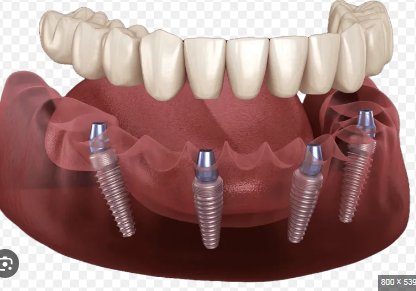

Dental implants are artificial tooth roots, typically made from titanium, that are surgically placed into the jawbone. They provide a sturdy foundation for permanent or removable replacement teeth, designed to blend seamlessly with natural teeth. Studies show that dental implants have a success rate of over 95% when performed by experienced specialists, making them a reliable option for long-term oral restoration.

The dental implant process generally involves several stages:

Initial Consultation and Imaging: Specialists evaluate oral health, jawbone condition, and overall suitability for implants.

Surgical Placement: The implant is inserted into the jawbone under local anesthesia or sedation.

Osseointegration Period: Over several months, the implant fuses with the bone, creating a strong foundation.

Restoration Placement: The final crown, bridge, or denture is attached, completing the smile restoration.